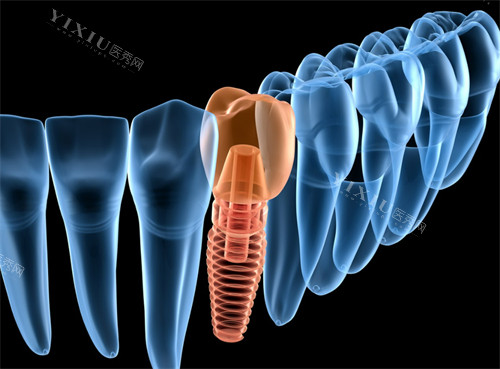

一、种植牙:多元植体,满足个性化需求

种植牙是修复缺失牙的理想方式,五邑中医院牙科提供多种植体品牌与价格选择。

韩国登腾种植体 2680 元起 / 颗,韩国奥齿泰种植体 3280 元起 / 颗,这两款植体性价比高,在临床应用广泛,适合多数患者的基础需求。

美国皓圣种植体 6500 元起 / 颗,德国贝格种植体 7200 元起 / 颗,欧美植体采用优质材料,初期稳定性好,使用寿命更长。

瑞士 ITI 种植体 10800 元起 / 颗,瑞典诺贝尔种植体 13800 元起 / 颗,作为高端植体代表,具备卓然的生物相容性和抗腐蚀性,适合对种植牙质量要求极高的患者。

半口种植牙根据植体数量与品牌,价格在 3 万 - 15 万元不等;全口种植牙价格区间为 6 万 - 30 万元。